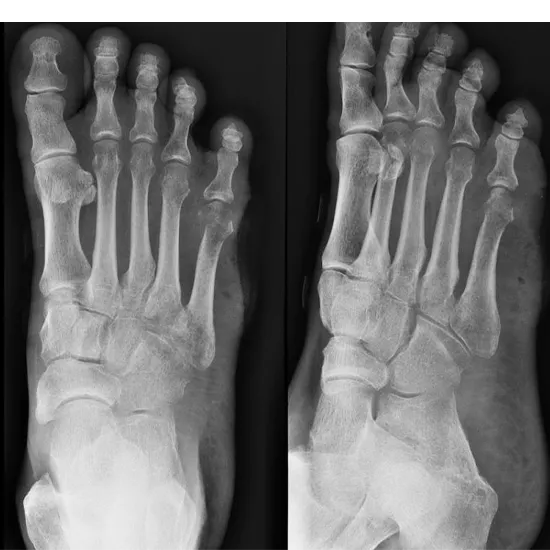

X-ray Left Foot AP/Oblique

A Left Foot AP & Oblique View X-ray is used to see the bones of the foot, including the ankle bones (tarsal bones), the front end of the foot (metatarsal bones), and the toes (phalanges), as well as the soft tissues (skin and muscles) surrounding it.